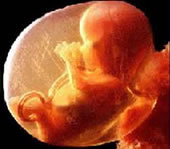

Развој бебе у стомаку мајке (фото) - улаз

Већина лекара који изводе чедоморства ради новца не дозвољавају мајкама да виде своје дете на ултразвуку нити да чују његове откуцаје срца да не би промениле одлуку.

78 % жена које виде ултра-звук бебе одбијају абортус! - погледајте